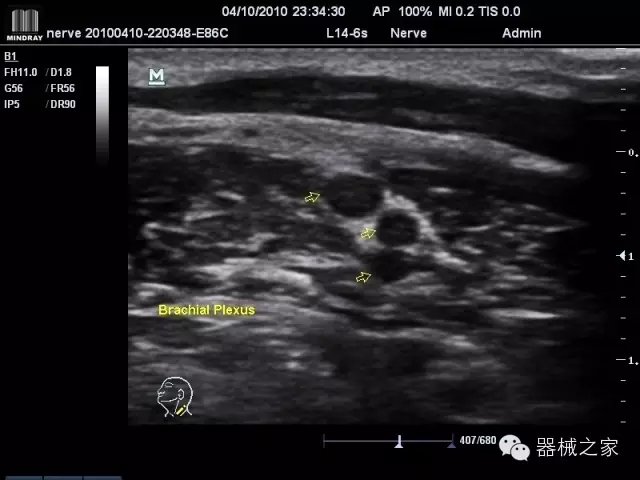

經(jīng)典產(chǎn)品:M7(星鉆)

臨床圖片賞析

產(chǎn)品特點(diǎn)

·裝載有采用Multi-Core多核處理的非嵌入式平臺(tái),成像效率大大提高,并且能夠給用戶帶來高速、多任務(wù)并行信號(hào)處理體驗(yàn);

·優(yōu)秀的圖像效果、強(qiáng)大的功能體驗(yàn)、豐富的探頭選擇、合理的便攜式設(shè)計(jì),全中文顯示及病人管理界面,使得M7在任何場合、任何時(shí)候都能快速響應(yīng)更好的心血管、腹部、婦產(chǎn)、小器官等常規(guī)超聲檢查以及肌骨、神經(jīng)、顱腦、術(shù)中等新興領(lǐng)域的使用需求;